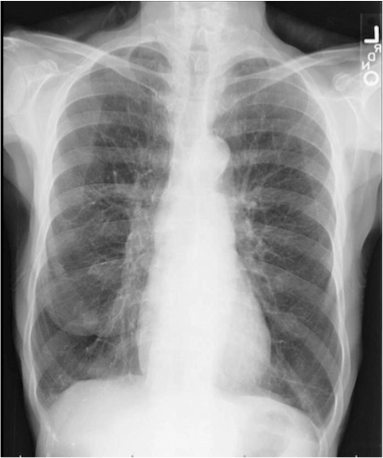

Please let me share a few interesting facts I have learned about lung cancer since discovering I have nodules in my own lungs. Nodules can be seen as a precursor to cancer. In my case they were found by getting a simple chest X-ray. Please get your lungs checked today! But when I recently asked my pulmonologist how common nodules are, she informed me that they are far more common than previously expected. How do we know this? So many more people have received X-rays and cat scans of their lungs in the past decade or so.

I also learned that, like me, as many as 20% of people who die from lung cancer in the United States every year have never smoked or used any other form of tobacco. In fact, if lung cancer in non-smokers had its own separate category, it would rank among the top 10 fatal cancers in the United States. Non-small cell lung cancer (NSCL) is the most common type of lung cancer, yet it’s difficult to detect early on because early-stage lung cancer often has no symptoms and is not detected with a chest X-ray. Positron emission tomography (PET) and CT scans can be more helpful in diagnosing lung cancer.